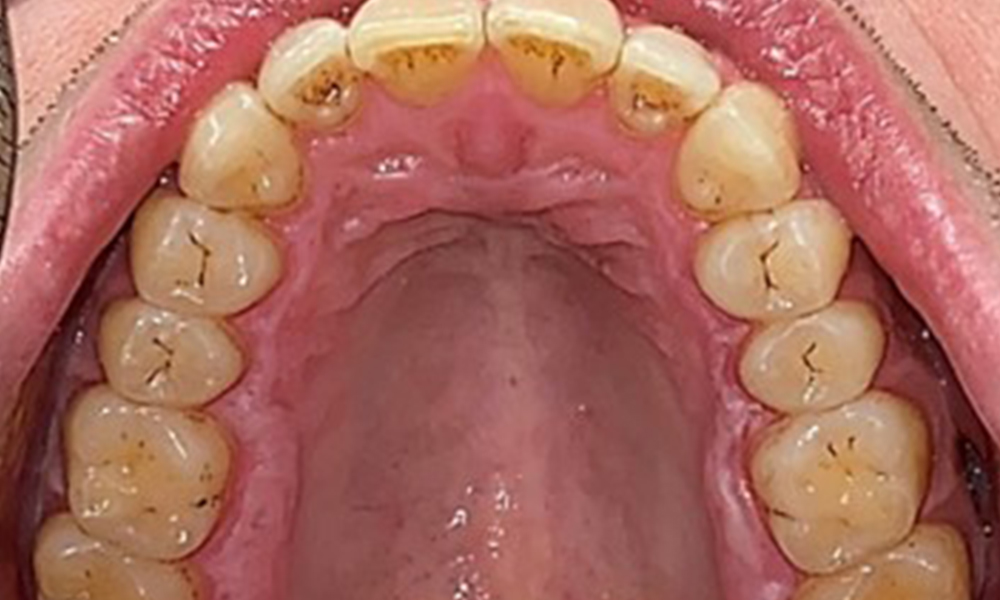

Extra- und Intraoraler Befund

Extraoral sind keine pathologischen Befunde festzustellen, intraoral zeigen sich bei der Frontalansicht im Bereich der keratinisierten Gingiva und am Übergang zur beweglichen Schleimhaut bräunlicheVerfärbungen (Abb. 2), welche auf den Nikotingenuss zurückzuführen sind. Am Gaumenbereich zeigen sich insbesondere im Bereich Oberkiefermolaren palatinal weißliche Schleimhautveränderungen, die ein Hinweis auf einen erhöhten Verhornungsgrad sind und ebenso auf den Nikotingenuss zurückzuführen sind. Die Zunge ist mit einem weiß-bräunlichen abwischbaren Belag versehen.

Dental zeigt sich ein vollbezahntes Gebiss mit 28 Zähnen. Auffällig sind Erosionen und Attritionen

(Abb. 4, Abb. 5). Der Patient trägt seit vielen Jahren nachts eine Schiene mit adjustiertem Aufbiss aufgrund Bruxismus. Die Erosionen sind auf den langjährigen Konsum isotonischer Getränke zurückzuführen. Parodontaler Knochenverlust und aktive kariöse Läsionen sind nicht vorhanden.